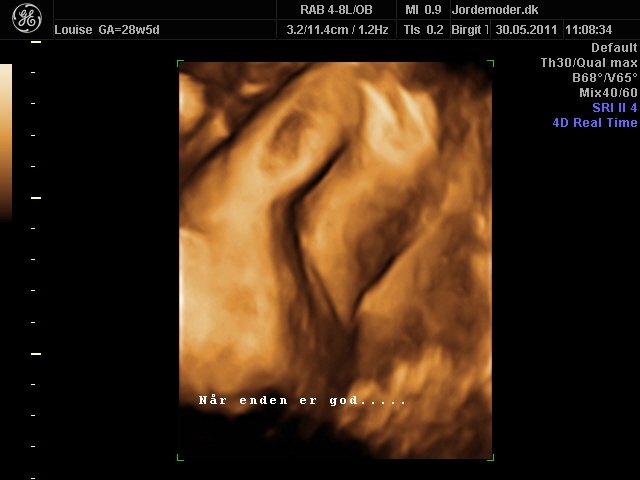

Moar2011

i uge 28

Vedhæftede fotos (klik for at se i fuld størrelse)